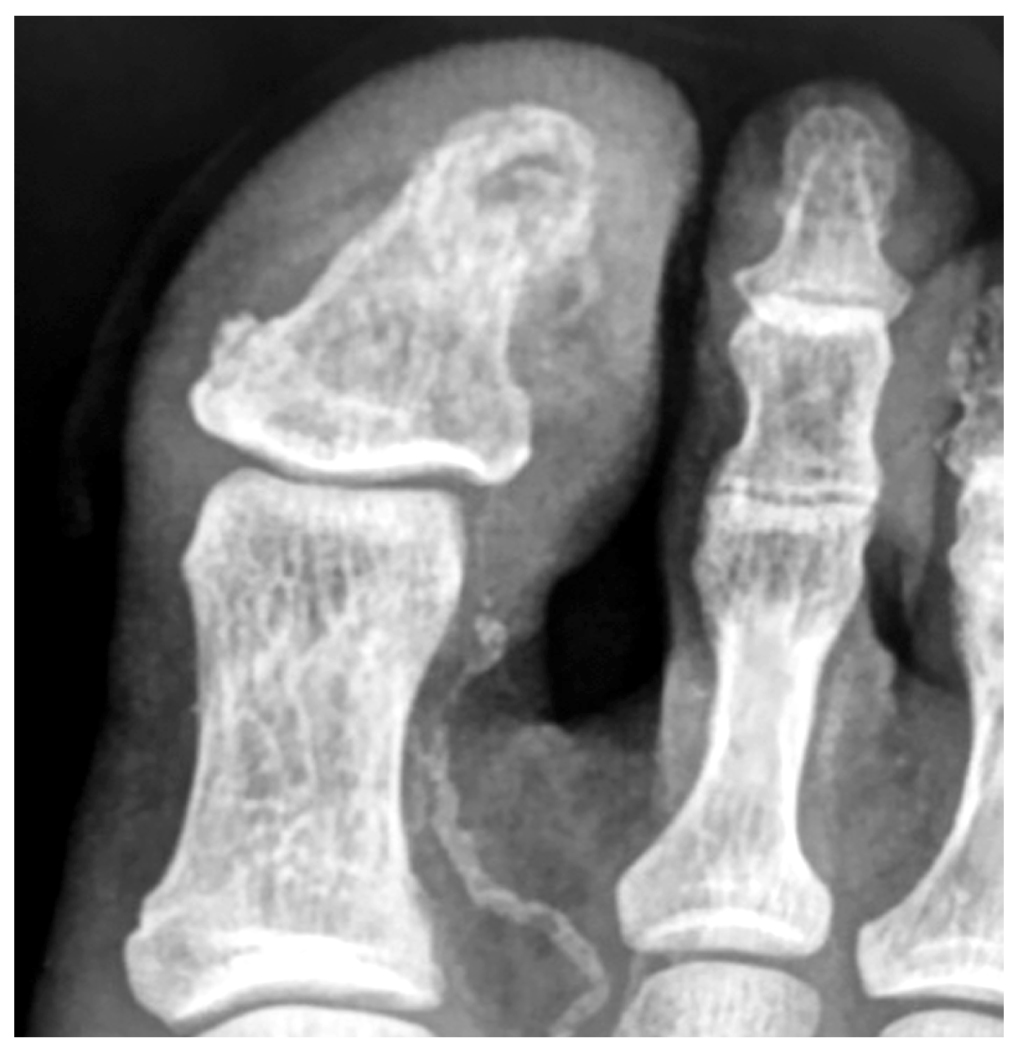

Рентгенография дистальных отделов нижней конечности слева. Выраженная деструкция концевой фаланги I пальца левой стопы (рис. 1).

Рис. 1. Рентгеновский снимок I пальца поражённой левой стопы перед началом амбулаторного лечения

Fig. 1. Radiograph of the I toe of the affected left foot, before starting the outpatient treatment